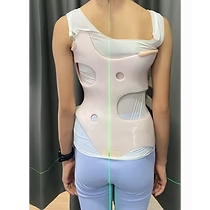

الضغط الصحيح لحزام اعوجاج العمود الفقري: الضلع أم الفقرة؟ عندما يُشخَّص الطفل أو المراهق بوجود اعوجاج في العمود الفقري، يبدأ الأهل في البحث عن أفضل طرق العلاج غير الجراحي. ويعد حزام اعوجاج العمود الفقري

ضغط حزام اعوجاج العمود الفقري : كيف يؤثر على العضلات والعظام والأقراص بين الفقرات؟ يعاني بعض الأطفال والمراهقين من اعوجاج العمود الفقري مجهول السبب عند المراهقين، وهي حالة يحدث فيها انحناء غير طبيعي في